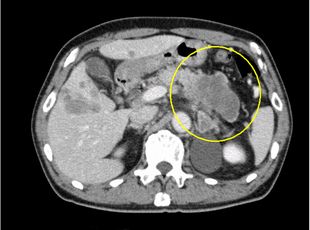

造影CT横断像(膵尾部がん)